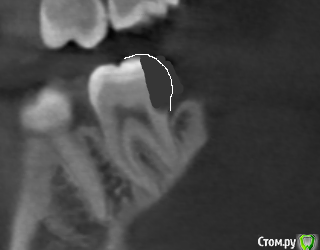

Александр23712 Опубликовано 3 октября, 2020 Поделиться Опубликовано 3 октября, 2020 (изменено) Всем здравствуйте! Я просматриваю частенько вопросы пациентов, ответы на них, недавно была тема вот с таким случаем (см. картинки). Тут вот я и задумался, мы это лечим как обычный второй класс, т.е. доступ с окклюзионной поверхности, сносим все, что выше, и восстанавливаем с помощью Супермата/Тоффльмайера/замковых матриц? При таких концевых дефектах получается и коффер не одеть? В теме был еще вариант про удаление-имплант, но это прям радикально мне кажется. Вот такое должно получиться решение?(картинка 3). Никак не могу смириться с тем, что в некоторых случаях надо иссечь своих тканей столько же, а то и больше, чем сам дефект Изменено 3 октября, 2020 пользователем Александр23712 Ссылка на комментарий

annda Опубликовано 4 октября, 2020 Поделиться Опубликовано 4 октября, 2020 Если получится получить доступ ,визуализацию и контроль , отдавив десну тефлоном, пилите тоннельным способом ультразвуком. Но высушить под адгезив все равно как следует не выйдет, потому только СИЦ. Откуда такой промежуток между молярами... Ссылка на комментарий

АнтонТЛТ Опубликовано 4 октября, 2020 Поделиться Опубликовано 4 октября, 2020 Можно хирургическое удлинение сделать, через пару недель будет сухо для адгезии Ссылка на комментарий